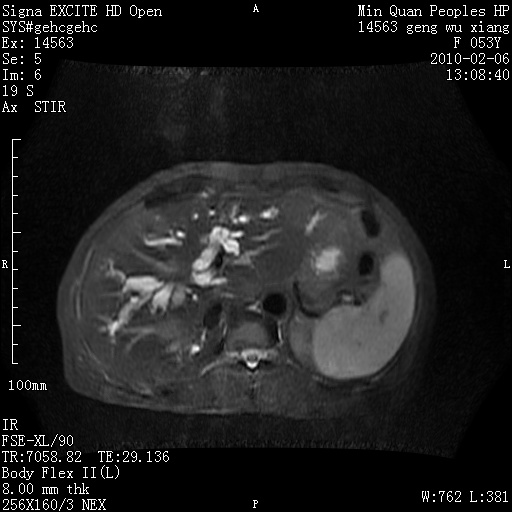

标题: MRI2762:胆道梗阻原因?

f,53y,全身黄染多日。

高位胆道梗阻 胆管癌可能性大

支持 高位胆道梗阻 胆管癌可能性大。